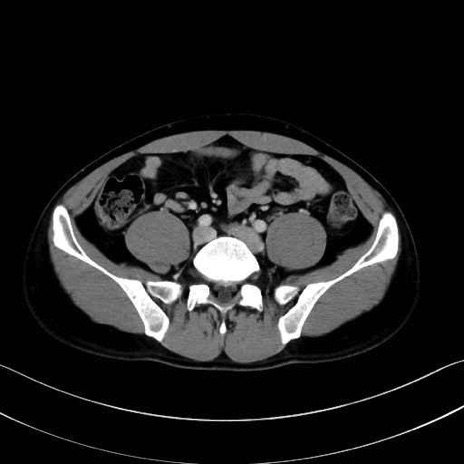

小殿筋 (Gluteus minimus)